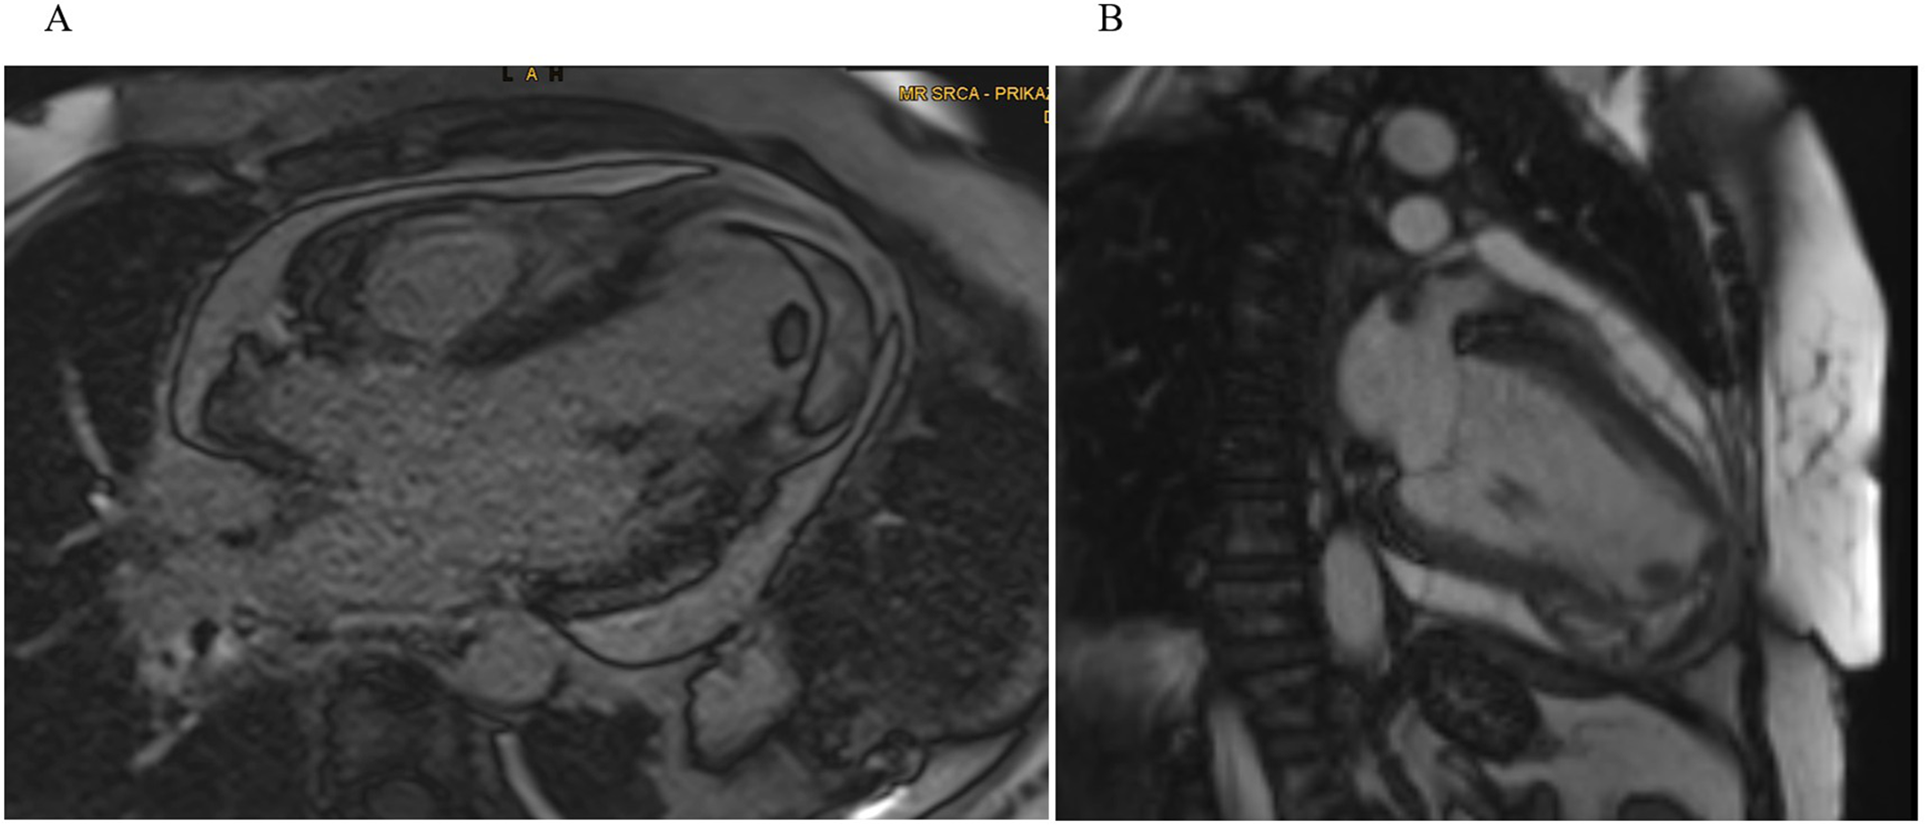

Upon admission back to the tertiary cardiac care unit (CCU), cardiac MRI on day 6 confirmed an inferoapical transmural MI extending into the septum, complicated by a large IDH (60 × 55 × 30 mm). An apical intracavitary thrombus measuring 10 mm was also identified. Findings of acute pericarditis (extensive inflammation and late gadolinium enhancement) and pericardial effusion (up to 15 mm) along the lateral wall of LV (Figure 2). Concurrently, aspirin at a dose of 100 mg was introduced for antiplatelet effects because of the suspicion of myocardial infarction as the primary event and colchicine was added for pericarditis management.

Figure 2

Cardiac MRI. (A) Four-chamber and (B) two-chamber views showing a well-demarcated hypointense lesion within the inferoapical wall extending into the septum, consistent with intramyocardial hemorrhage and a clearly defined intracavitary thrombus visible at the LV apex.